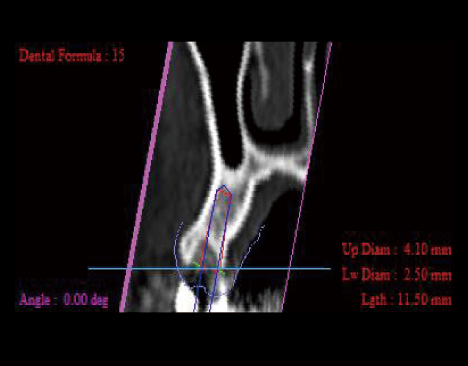

インプラント

歯科インプラントとは、失った歯の部分にチタン製の人工歯根(インプラント)を埋め入れて、歯本来の機能や見た目を取り戻す治療方法のことをいいます。 失った歯の部分を治療しますので、周囲の歯に負担をかけることがありません。 また、これまでにあった歯と同じような役割を果たしますので、噛む力を分散させ、残っている自分の歯を守ることにもなります。